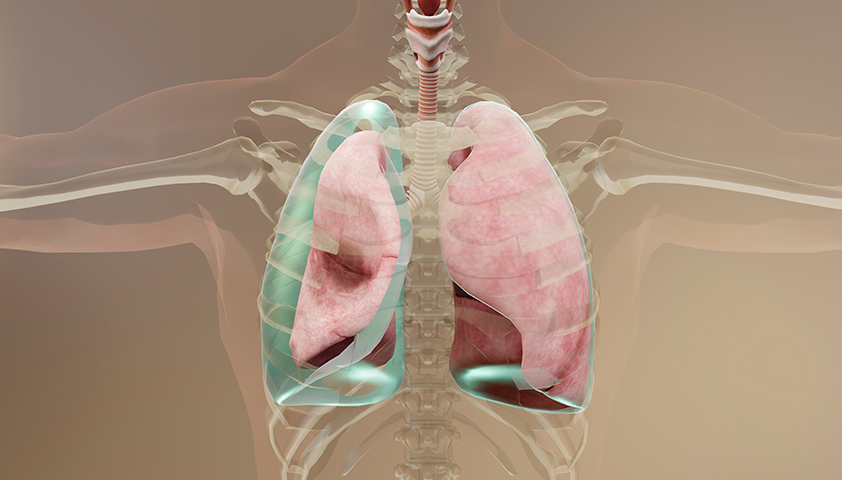

При пневмотораксе воздух проникает в герметичное пространство вокруг лёгкого — плевральную полость. Это приводит к сдавливанию дыхательного органа, из-за чего он не может полностью расправиться при вдохе. В результате нарушается дыхание, а в тяжёлых случаях может возникнуть угроза для жизни.

При пневмотораксе баланс давлений между плевральной полостью и лёгким нарушается — и оно опадает, как сдувшийся шарик

Напряжённый пневмоторакс — одно из самых грозных последствий. При этом состоянии воздух активно поступает в плевральную полость по принципу одностороннего клапана и не может выйти из неё. Воздуха скапливается так много, что лёгкое сжимается, а сердце и сосуды смещаются в сторону. Человек начинает задыхаться — падает давление, учащается пульс, синеет кожа. Без срочной помощи возможна потеря сознания и даже остановка сердца.